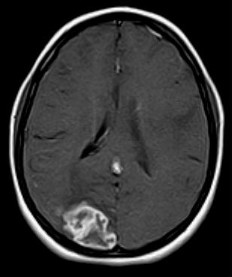

September 2005 - Intracerebral Tuberculomas

There is a conglomeration of lesions in the right temporo-parieto-occipital and left frontal lobes. These are hypointense on the T2W images and reveal a whorl or bunch of grapes type of enhancement. Note is made of perilesional edema.

On MRI

On plain MRI, granulomas usually appear isointense to gray matter on the T1W images and may have a slightly hyperintense rim (probably due to the presence of paramagnetic substances). On T2W images, the tuberculomas exhibit variable signal. They are often isointense or hypointense to brain parenchyma and it is postulated that this relative hypointensity is related to T2 shortening by paramagnetic free radicals produced by macrophages, which are heterogeneously distributed throughout the caseous granuloma. The diminished signal on T2W images may also be due to the mature tuberculoma being of greater cellular density than brain. Granulomas may also be hyperintense to brain on T2-weighted images; this is likely due to a greater degree of central liquefactive necrosis in these lesions. Edema surrounding tuberculomata is relatively more prominent in the early stages of granuloma formation.

Post contrast (gadolinium) images of TB granulomas demonstrate intense nodular and ring-like enhancement. Healed tuberculomas may calcify in up to 20% of cases and these are usually more evident on CT than MRI. On MRI, the calcifications are more evident on gradient-echo than on spin-echo imaging. Atrophy is frequently a long-term sequelae of tuberculous CNS infection. Full resolution of cerebral tuberculomas requires months to years of medical therapy. The length of time required is related more to the size of the original lesion than to any other single factor.